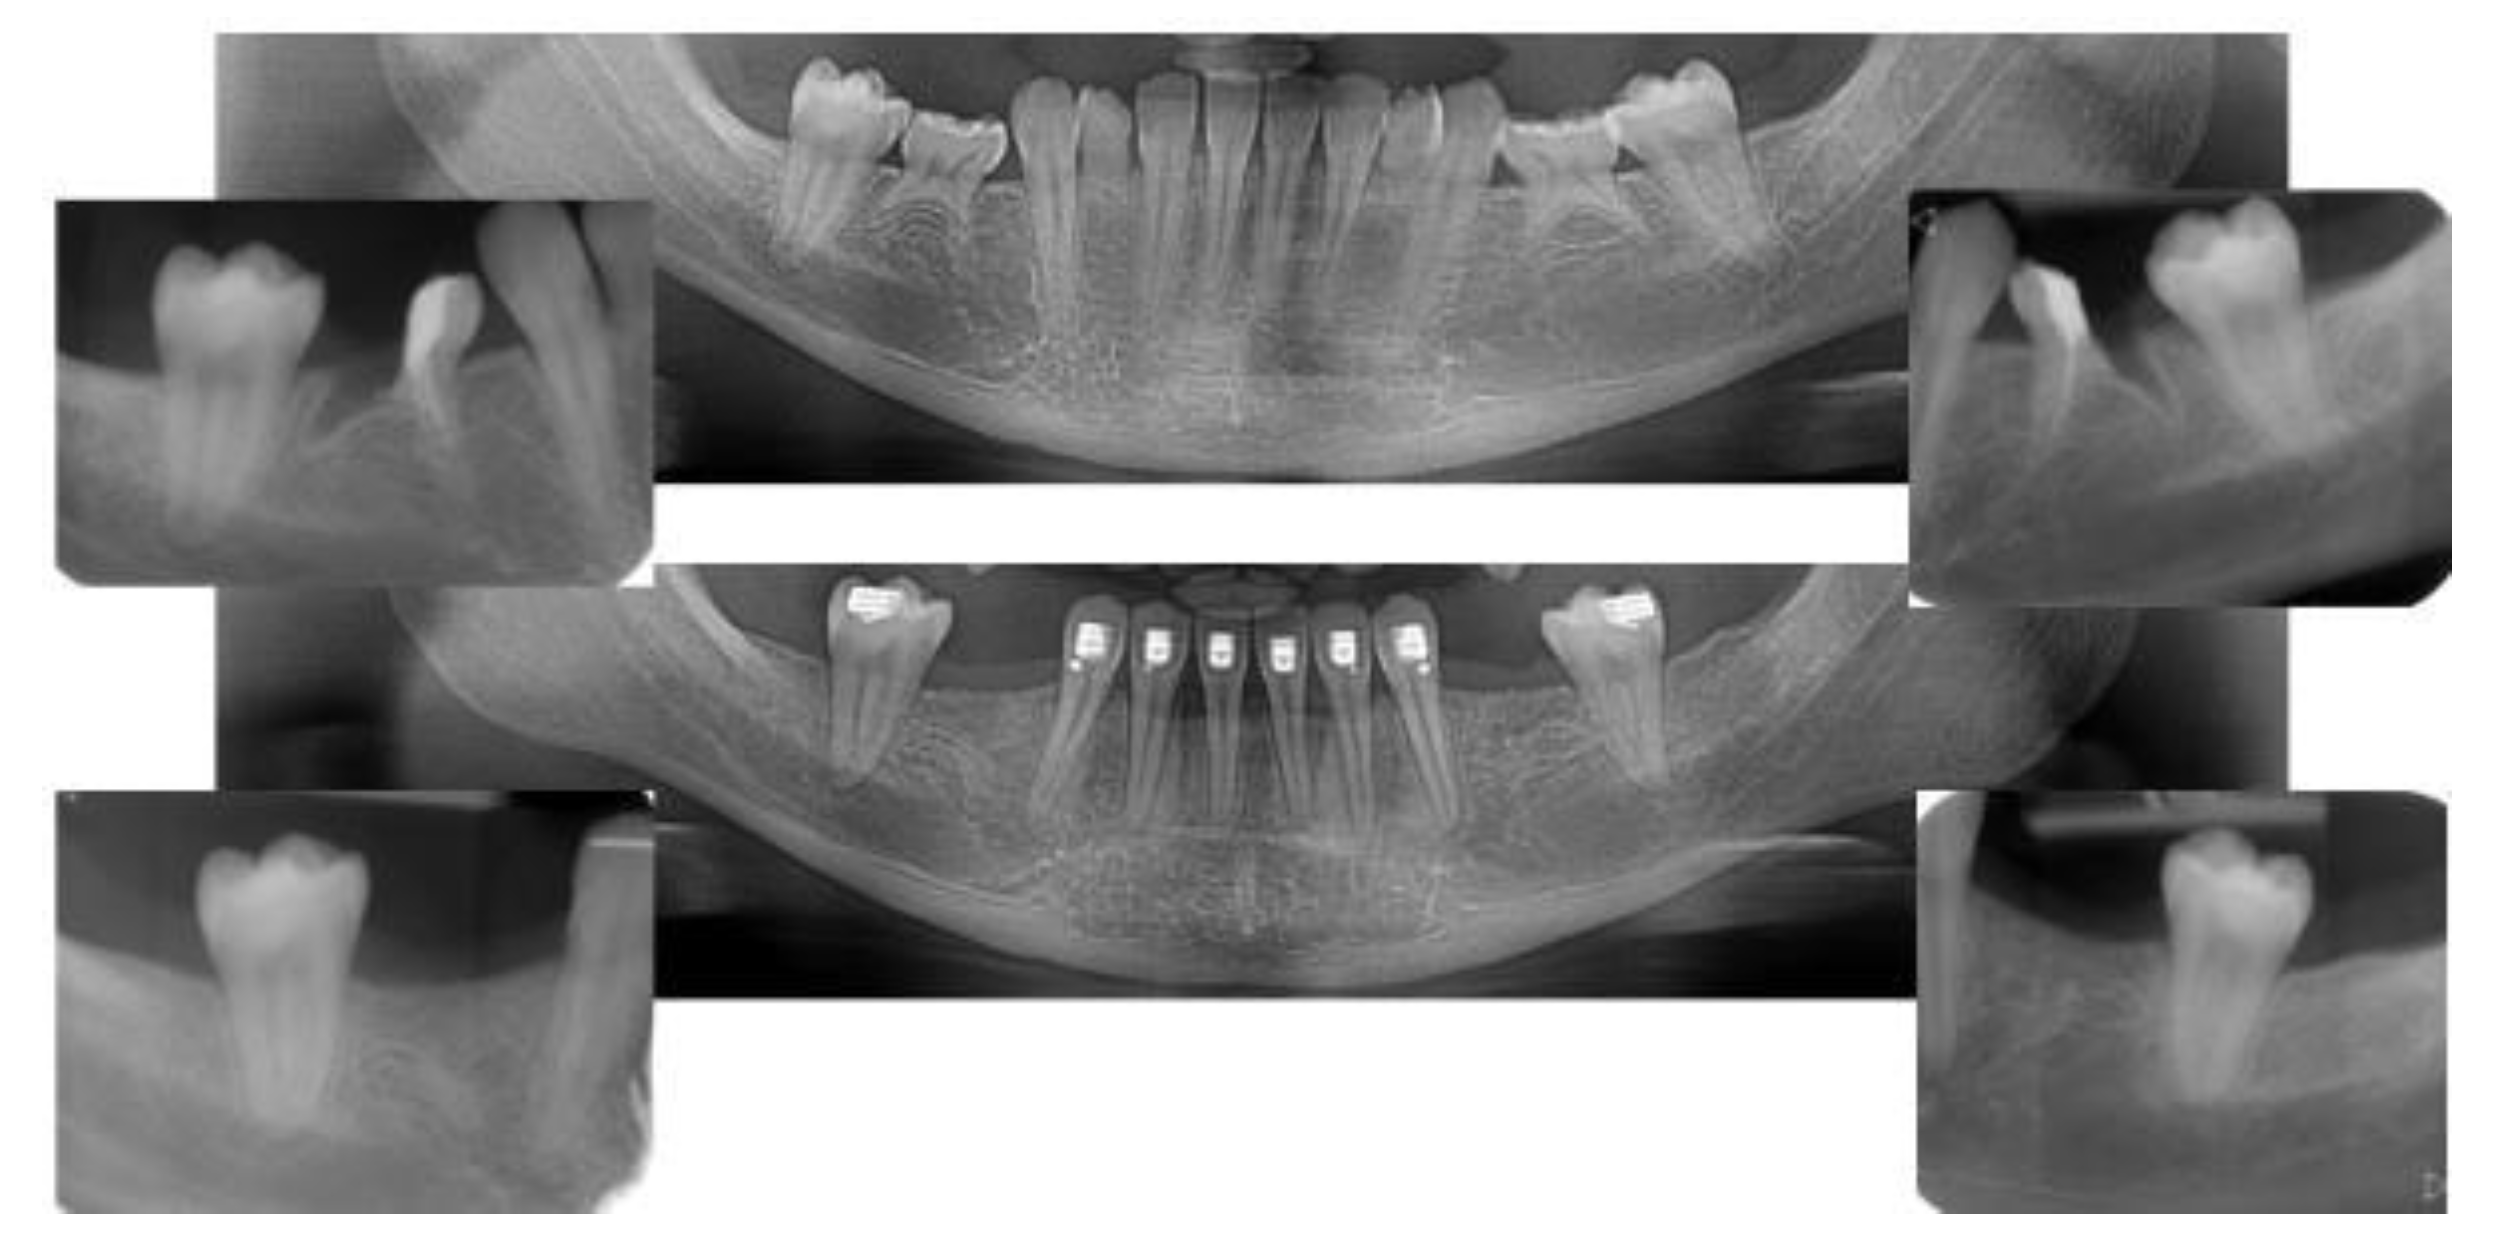

2.4.1. Radiographic Measurements

3.2. Marginal Bone Level Outcomes